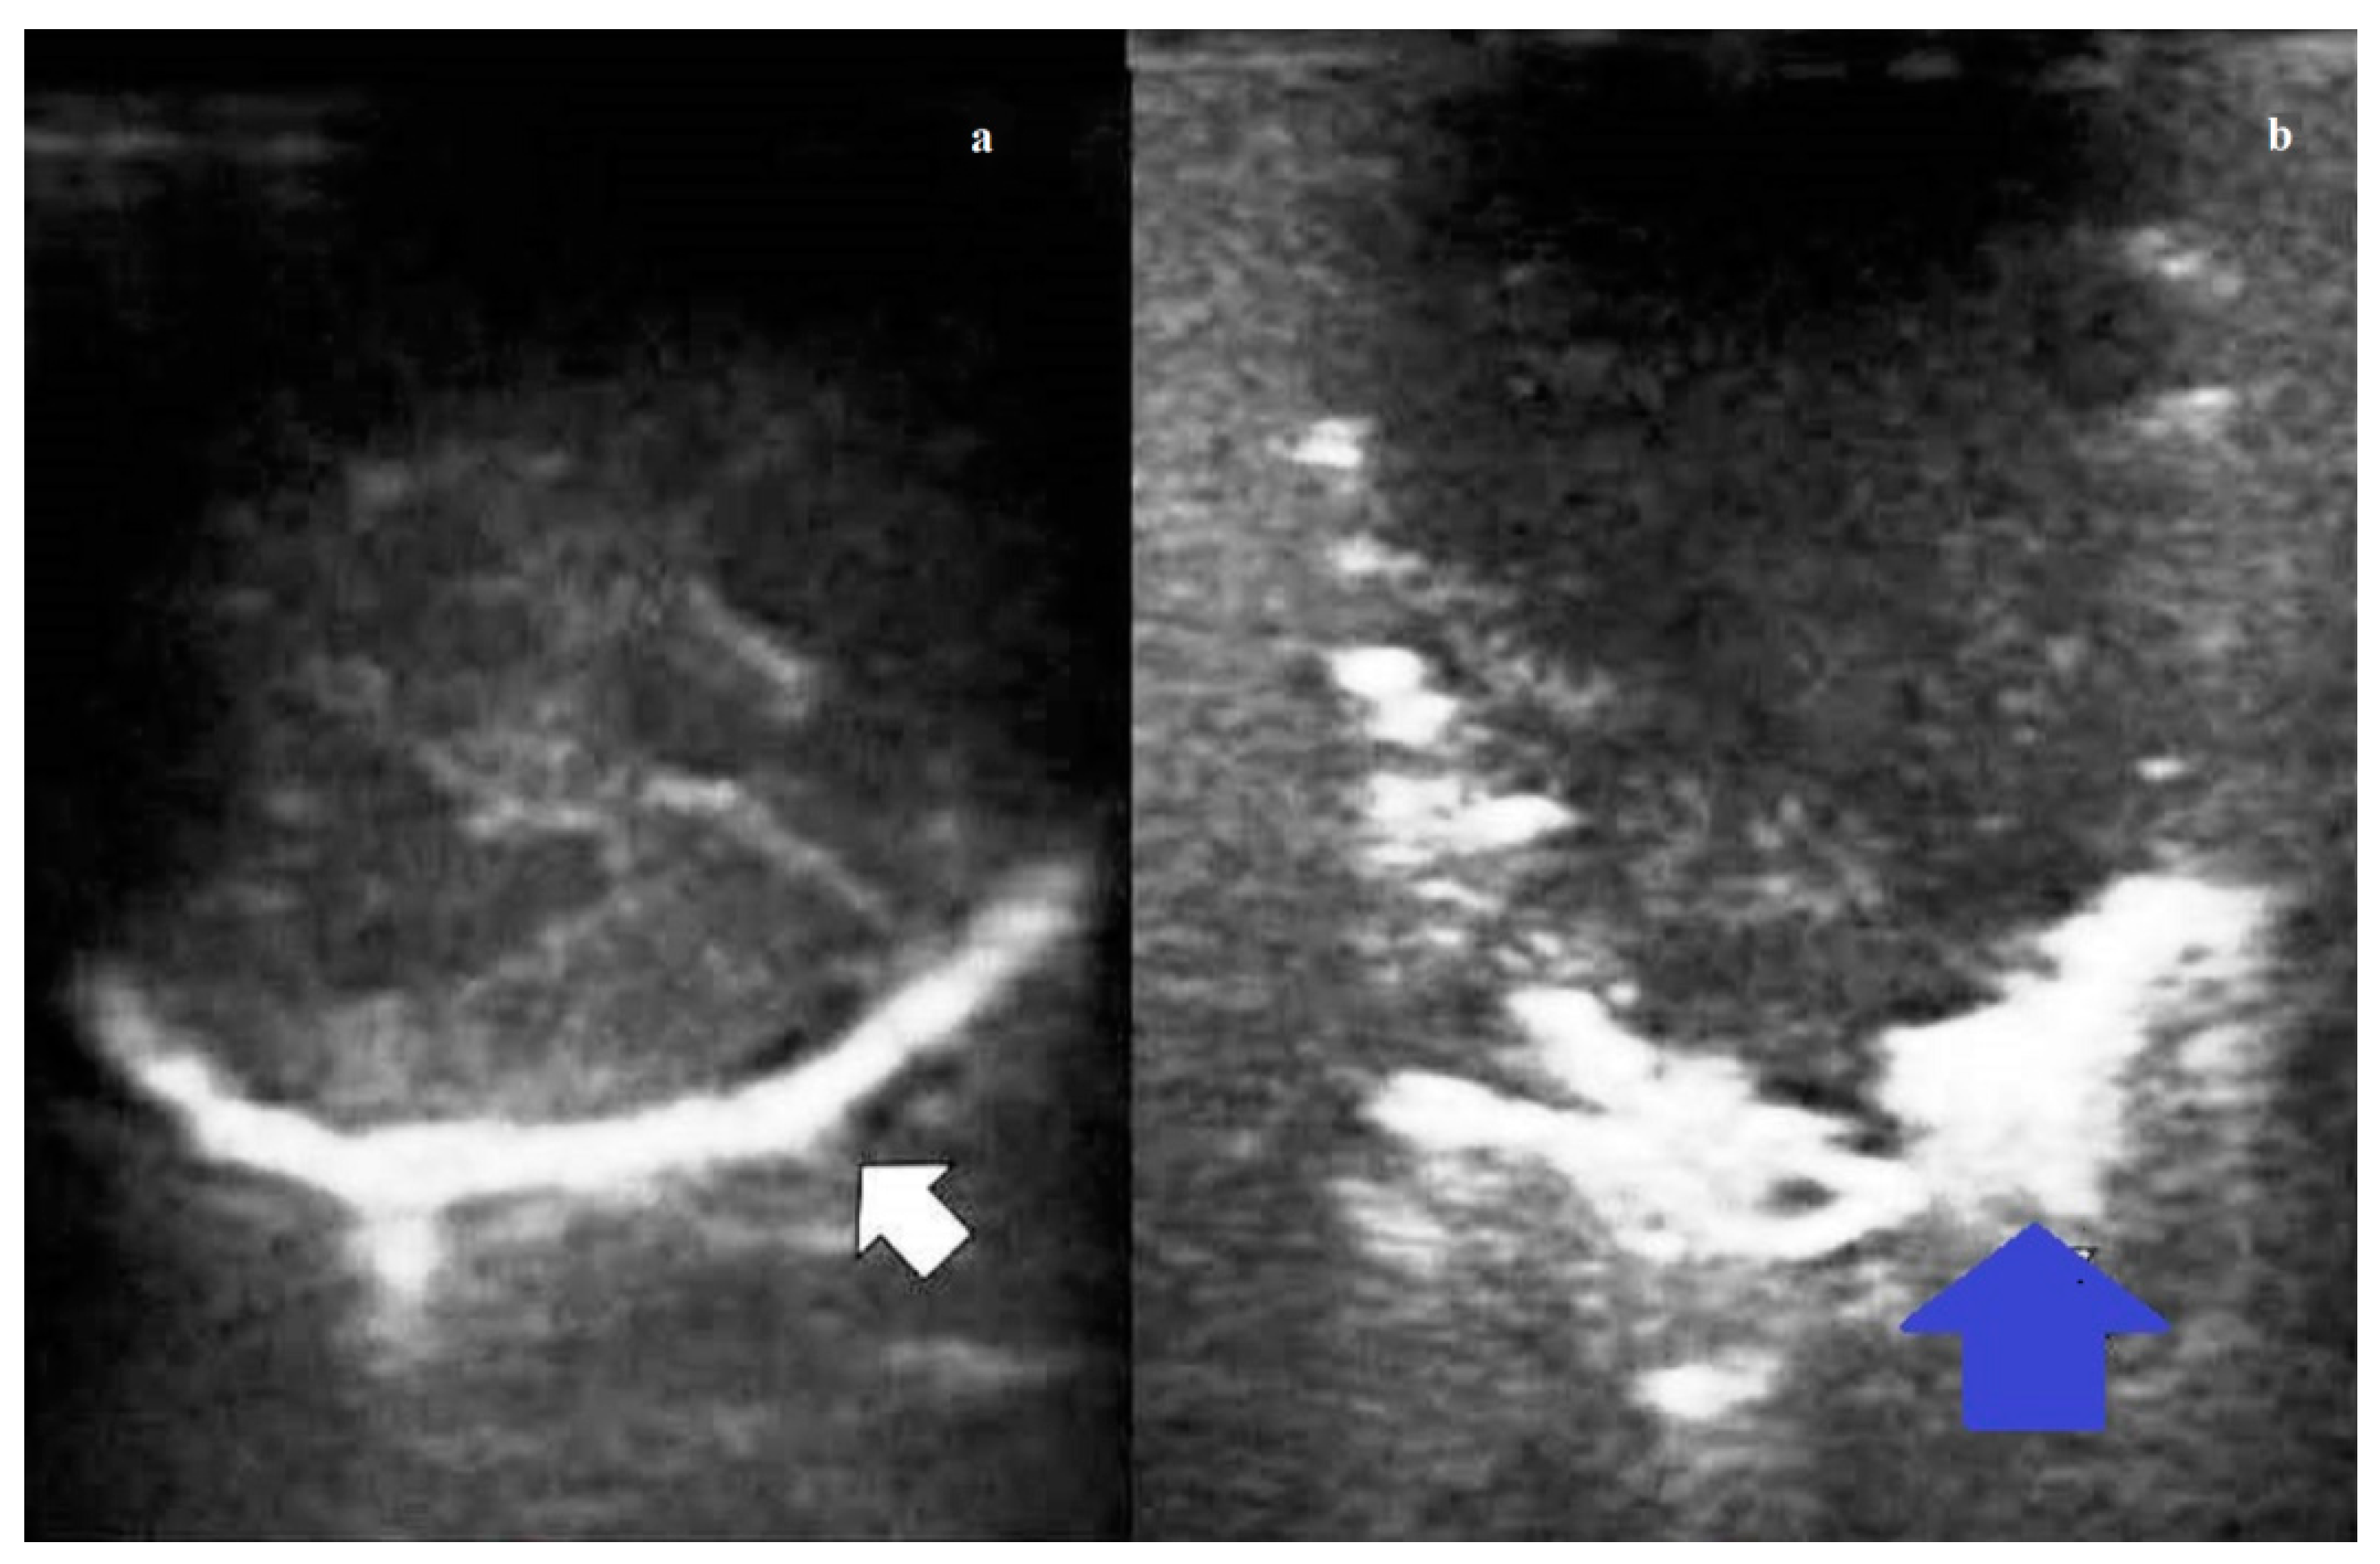

According to the ILU pattern, 125 (95.42%) nodules were classified as hypoechoic and six (4.58%) as hyperechoic. Among the hypoechoic nodules, 37 (28.24%) had intralesional hyperechoic spots. Benign nodules were in the vast majority of cases (94.12%) hypoechoic, with internal hyperechoic spots only in 38.24% of cases; they had regular rounded shape in all cases, and no jagged margins in 91.18% of cases. Malignant nodules were mostly hypoechoic (96.67% of cases) with jagged margins (68.33%). Internal hyperechoic spots were found only in the 21.65% of cases. A regular rounded shape was observed in roughly the half (53.33%) of cases (Figure 2). Metastases were mostly hypoechoic (94.59%), with jagged margins (100.00%). Internal hyperechoic spots were seldom assessed (29.73%) (Table 3).

Figure 2. (a) Intraoperative lung ultrasound (ILU) scan showing a hyperechoic pulmonary nodule (white arrow) with a regular rounded shape and well-defined margin. The final histological diagnosis was pulmonary hamartoma. (b) Intraoperative lung ultrasound (ILU) scan showing a hypoechoic nodule (blue arrow) with irregular shape and jagged margin. The final histological diagnosis was pulmonary adenocarcinoma.